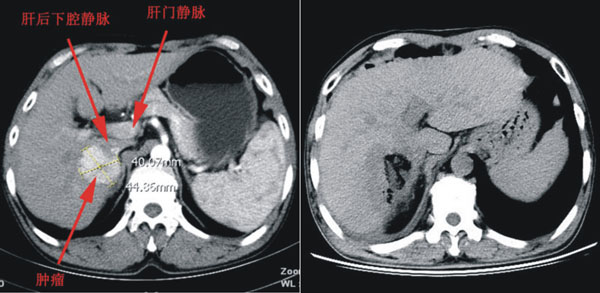

患者是一名来自澄县的52岁男性,在当地医院诊断为原发性肝癌、乙肝肝硬化。肿瘤大小约4.5×4×4cm,位于肝脏Ⅵ、Ⅶ段之间,紧贴肝后下腔静脉,前方是第一肝门,上方毗邻第二肝门,右侧有门静脉右后支及胆道跨过,解剖部位非常复杂,是肝脏手术的相对禁区。且患者有慢性肝病,肝储备功能差,难以耐受半肝切除手术,所以手术既要保证肝癌的根治性切除,又要考虑患者术后肝功能的恢复,手术风险大,成功率很低,如术中稍有不慎可能会造成难以挽救的后果。因此之前患者辗转西安多家医院均被告知手术难度大,建议转院。黎一鸣教授接诊该患者后,经过慎重的的评估,认为手术切除的的机会较大。入院后,针对患者的病情及影像学资料,普外科对患者拟定了精密的手术规划,并做了精细的术前准备。

术前增强CT及冠状位重建检查

11月21日,由黎一鸣教授、刘清峰副主任医师、陆宏伟副主任医师、李华主治医师对患者实施了肝癌切除术。术中紧贴下腔静脉将肝脏肿瘤游离至第二肝门的下方,在术中B超的引导下,在肝内各个脉管之间的区域,以精准的定位和精细的操作在肝内选择一个安全并尽可能达到根治目的的切面。由于准备充分,整个手术过程有条不紊、配合严密,历时2个半小时,术中出血300ml,完整切除了肿瘤。手术过程未阻断肝门,最大程度的保护了患者的肝功能。术后患者很快清醒拔管,生命体征平稳,目前康复良好,各项检查指标均趋于正常,拟于近日出院。

术后CT影像学对比